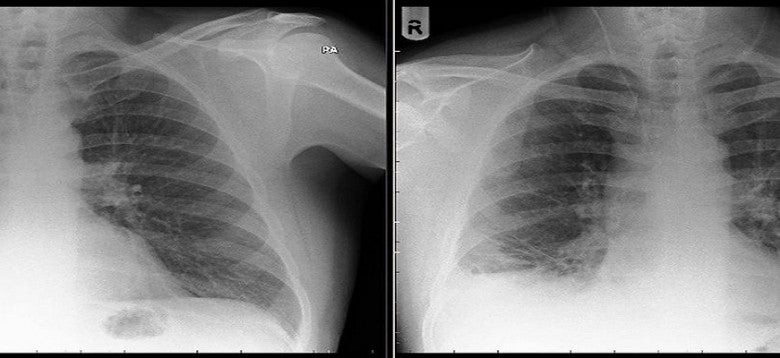

Οι γιατροί νόμιζαν ότι είχε καρκίνο του πνεύμονα, αλλά αντί για όγκο βρήκαν… (εικόνα)

Οι γιατροί του Royal Preston Hospital στο Λάνκασιρ της βορειοδυτικής Αγγλίας έστειλαν άρον-άρον για εξετάσεις έναν ασθενή που υποπτεύονταν ότι είχε προσβληθεί από καρκίνο των πνευμόνων. ...